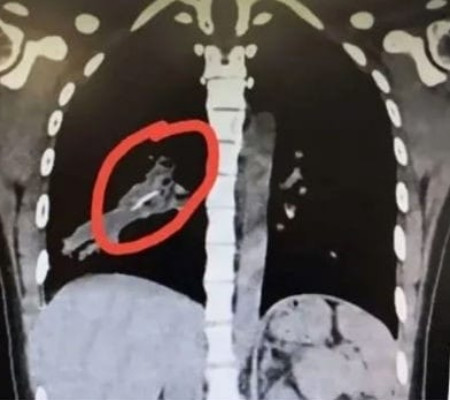

O responsável por ajudar a jovem a encontrar a solução para a condição foi o vice-chefe de cirurgia cardiotorácica do hospital. O dr. Wang Jiyong resolveu pedir novas tomografias para avaliar melhor a condição e verificar o que, de fato, estaria provocando as crises de tosse.

Identificada a causa pouco comum, o médico cirurgião realizou um procedimento de broncoscopia na jovem para recuperar o fragmento de osso que, segundo ele, parece ser de pato ou galinha.